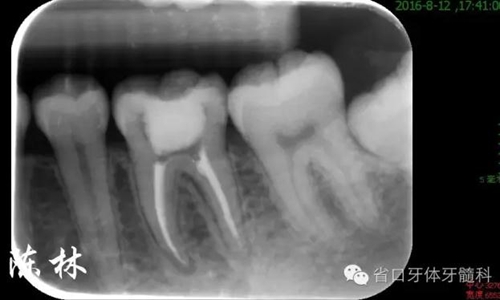

(圖7)根充片

處理:36橡皮障隔離,顯微鏡下去暫封,用賽特力超聲波治療儀ET18D工作尖清理髓室,DG16探查髓底,探及3個根管口(MB、ML、D),WAVEONE鎳鈦器械根管預(yù)備(25#),1%次氯酸鈉+NS交替沖洗,超聲蕩洗,吸干,試尖。AHplus+熱牙膠連續(xù)波垂直加壓充填法充填根管,棉球ZOE暫封。根充完成片示根管適填,約1周后復(fù)診。